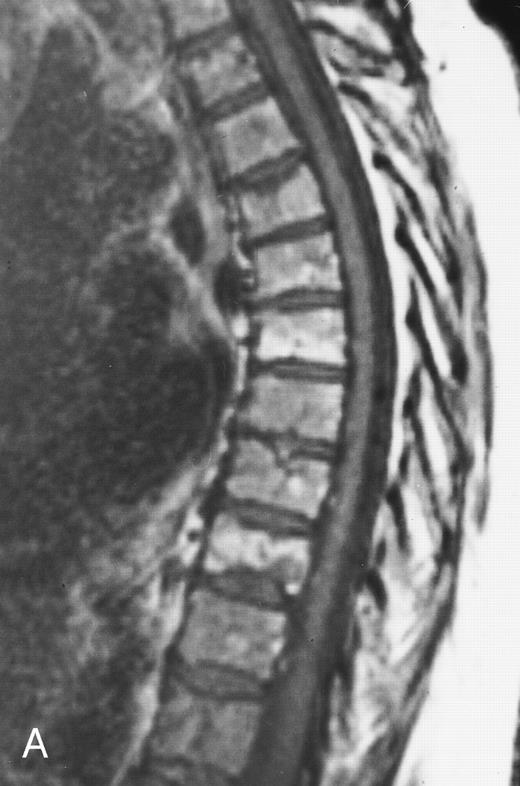

Normal appearance of spinal bone marrow in a 45-year-old woman: T1-weighted (500/11, TR/TE) (A) and T2-weighted, fat-suppressed fast spin echo (4000/96, TR/TE, ET 16) (B) sagittal MR images of the lumbar spine. Note increased signal of the vertebral bodies, relative to the intervertebral discs in (A) and increased deposition of fatty marrow around the basivertebral veins (arrowheads). On the T2-weighted image, normal intervertebral discs are brighter than the vertebral bodies; low signal in the L4-L5 and L5-S1 discs is due to degenerative changes (arrows).